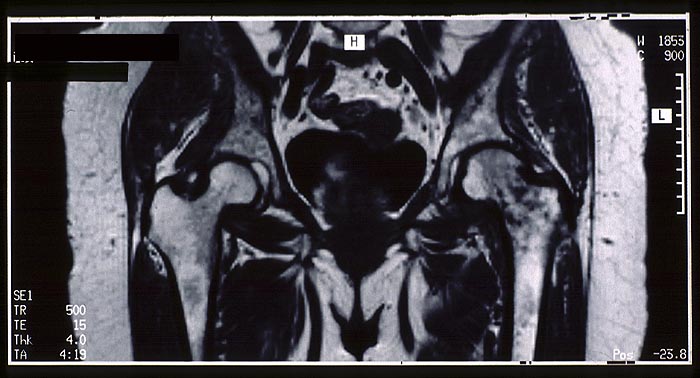

PathoPic – image database / PathoPic ID 5032 - Femurkopfnekrose links

Femurkopfnekrose links

vaskulär / Durchblutungsstörung

Knochen, Femur

Knochen, Knorpel, Gelenke

Klinik

Starke Hüftschmerzen links seit ca.

2 Monaten, zuvor gelegentlich Coxarthrosebeschwerden.

Sz-Lokalisation v. a. inguinal und tiefglutäal.